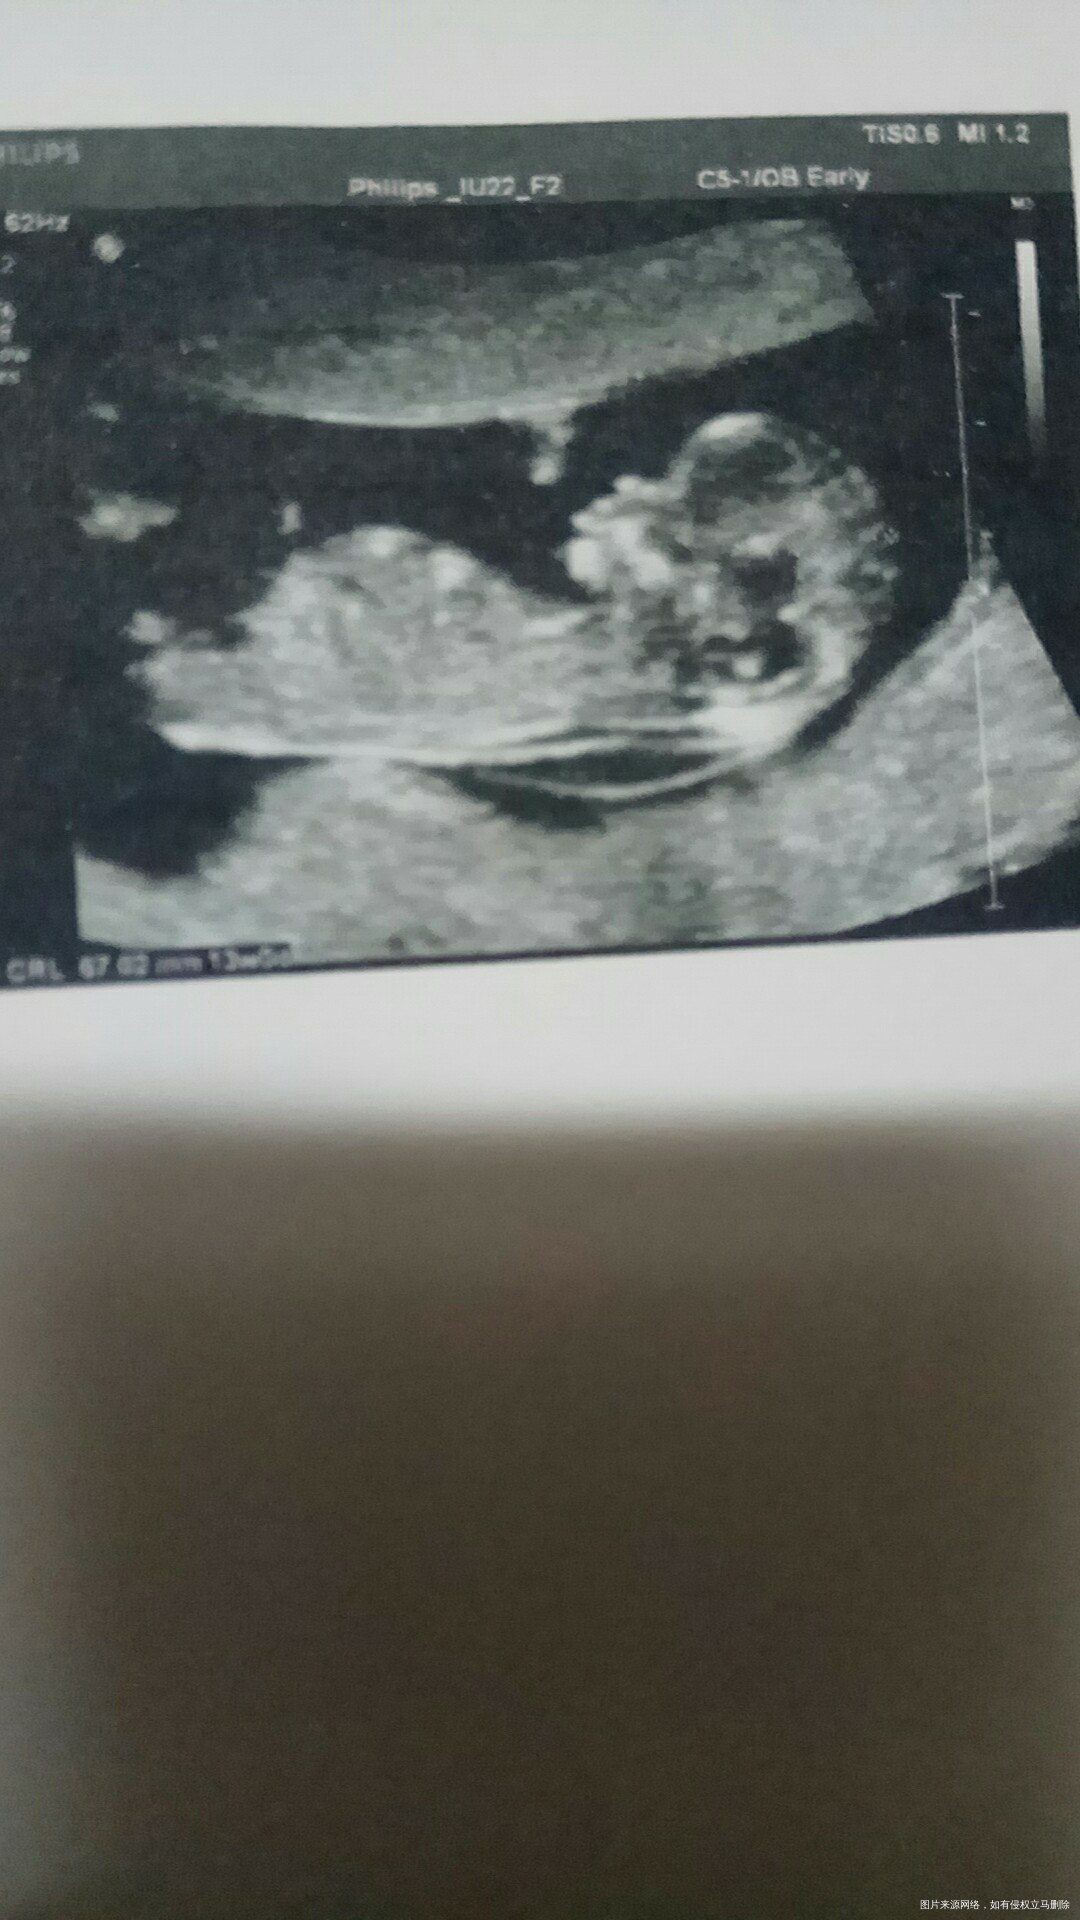

12月14号顺利通过nt✌宝宝很乖,nt一次通过,看到小可爱的模样,瞬间觉得真的怀孕了😂